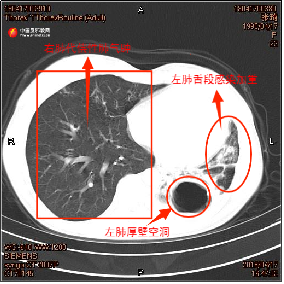

2018年4月第二次确诊肺结核时,张琦的痰培养结果证实其合并烟曲霉菌感染,时任住院医生张洋回忆起当时的治疗困境称:“张琦第二次确诊为复发性耐药肺结核,我们为她制定了针对性治疗方案,并增加了抗真菌的口服药。”治疗期间张琦多次拍摄的胸部CT片,也记录了其左肺病情恶化。张琦左肺下叶空洞逐渐变大,肺叶萎缩,感染逐渐加重。

▲左图为张琦2017年4月胸部CT,右图为张琦2018年4月胸部CT